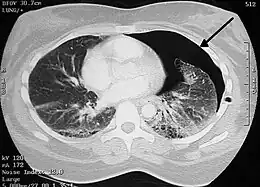

Image from a computed tomography (CT) scan of the chest. On the right (left side of the patient) there is a black area suggesting free air inside the chest

CT scan of the chest showing a pneumothorax on the person's left side (right side on the image). A chest tube is in place (small black mark on the right side of the image), the air-filled pleural cavity (black) and ribs (white) can be seen. The heart can be seen in the center.